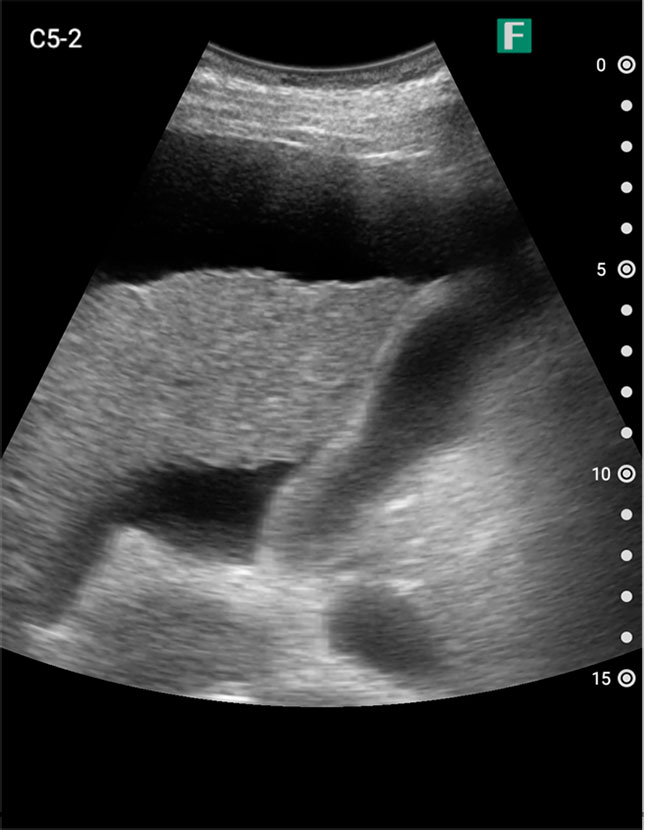

夜間、腹痛を主訴に高齢の男性が救急外来にいらっしゃいました。その方は尿道カテーテルが入っており、頻繁にカテーテルの閉塞を起こしている病歴がありました。

視診を行い下腹部に軽度の膨隆が確認できましたが体外から出ているカテーテルには明らかな閉塞を認めませんでした。そこで、iViz airで観察したところ、膀胱内に約400mlの残尿を認めカテーテル閉塞による腎後性腎不全と診断を確定させることができました。尿道カテーテルを抜去した際、外見からは見えないカテーテルの先端部分に沈殿物を認め、閉塞の原因であるとわかりました。その後尿道カテーテルの交換を行うと残尿の排出ともに腹痛は消失し、無事に帰宅されました。iViz airでの観察が尿閉の確定診断につながった症例です。